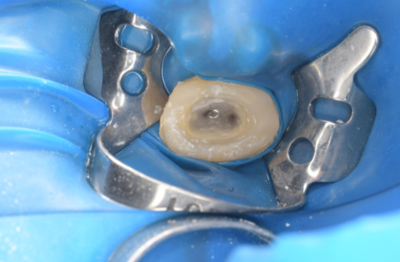

初診時デンタルX線写真とCT画像。

根管外に不透過像とそれを取り囲む透過像を認める。

コアを除去すると、分岐部へつながるパーフォレーションを認めた。

これが排膿の原因であったため、保存は困難と判断した。